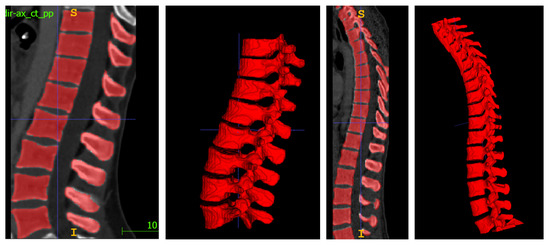

4.1. Spine Segmentation

- 3D Multi-class Segmentation. Centroids are used in a k-nearest neighbors (k-NN) classifier to produce a 3D segmentation map in which each vertebra has its own label.